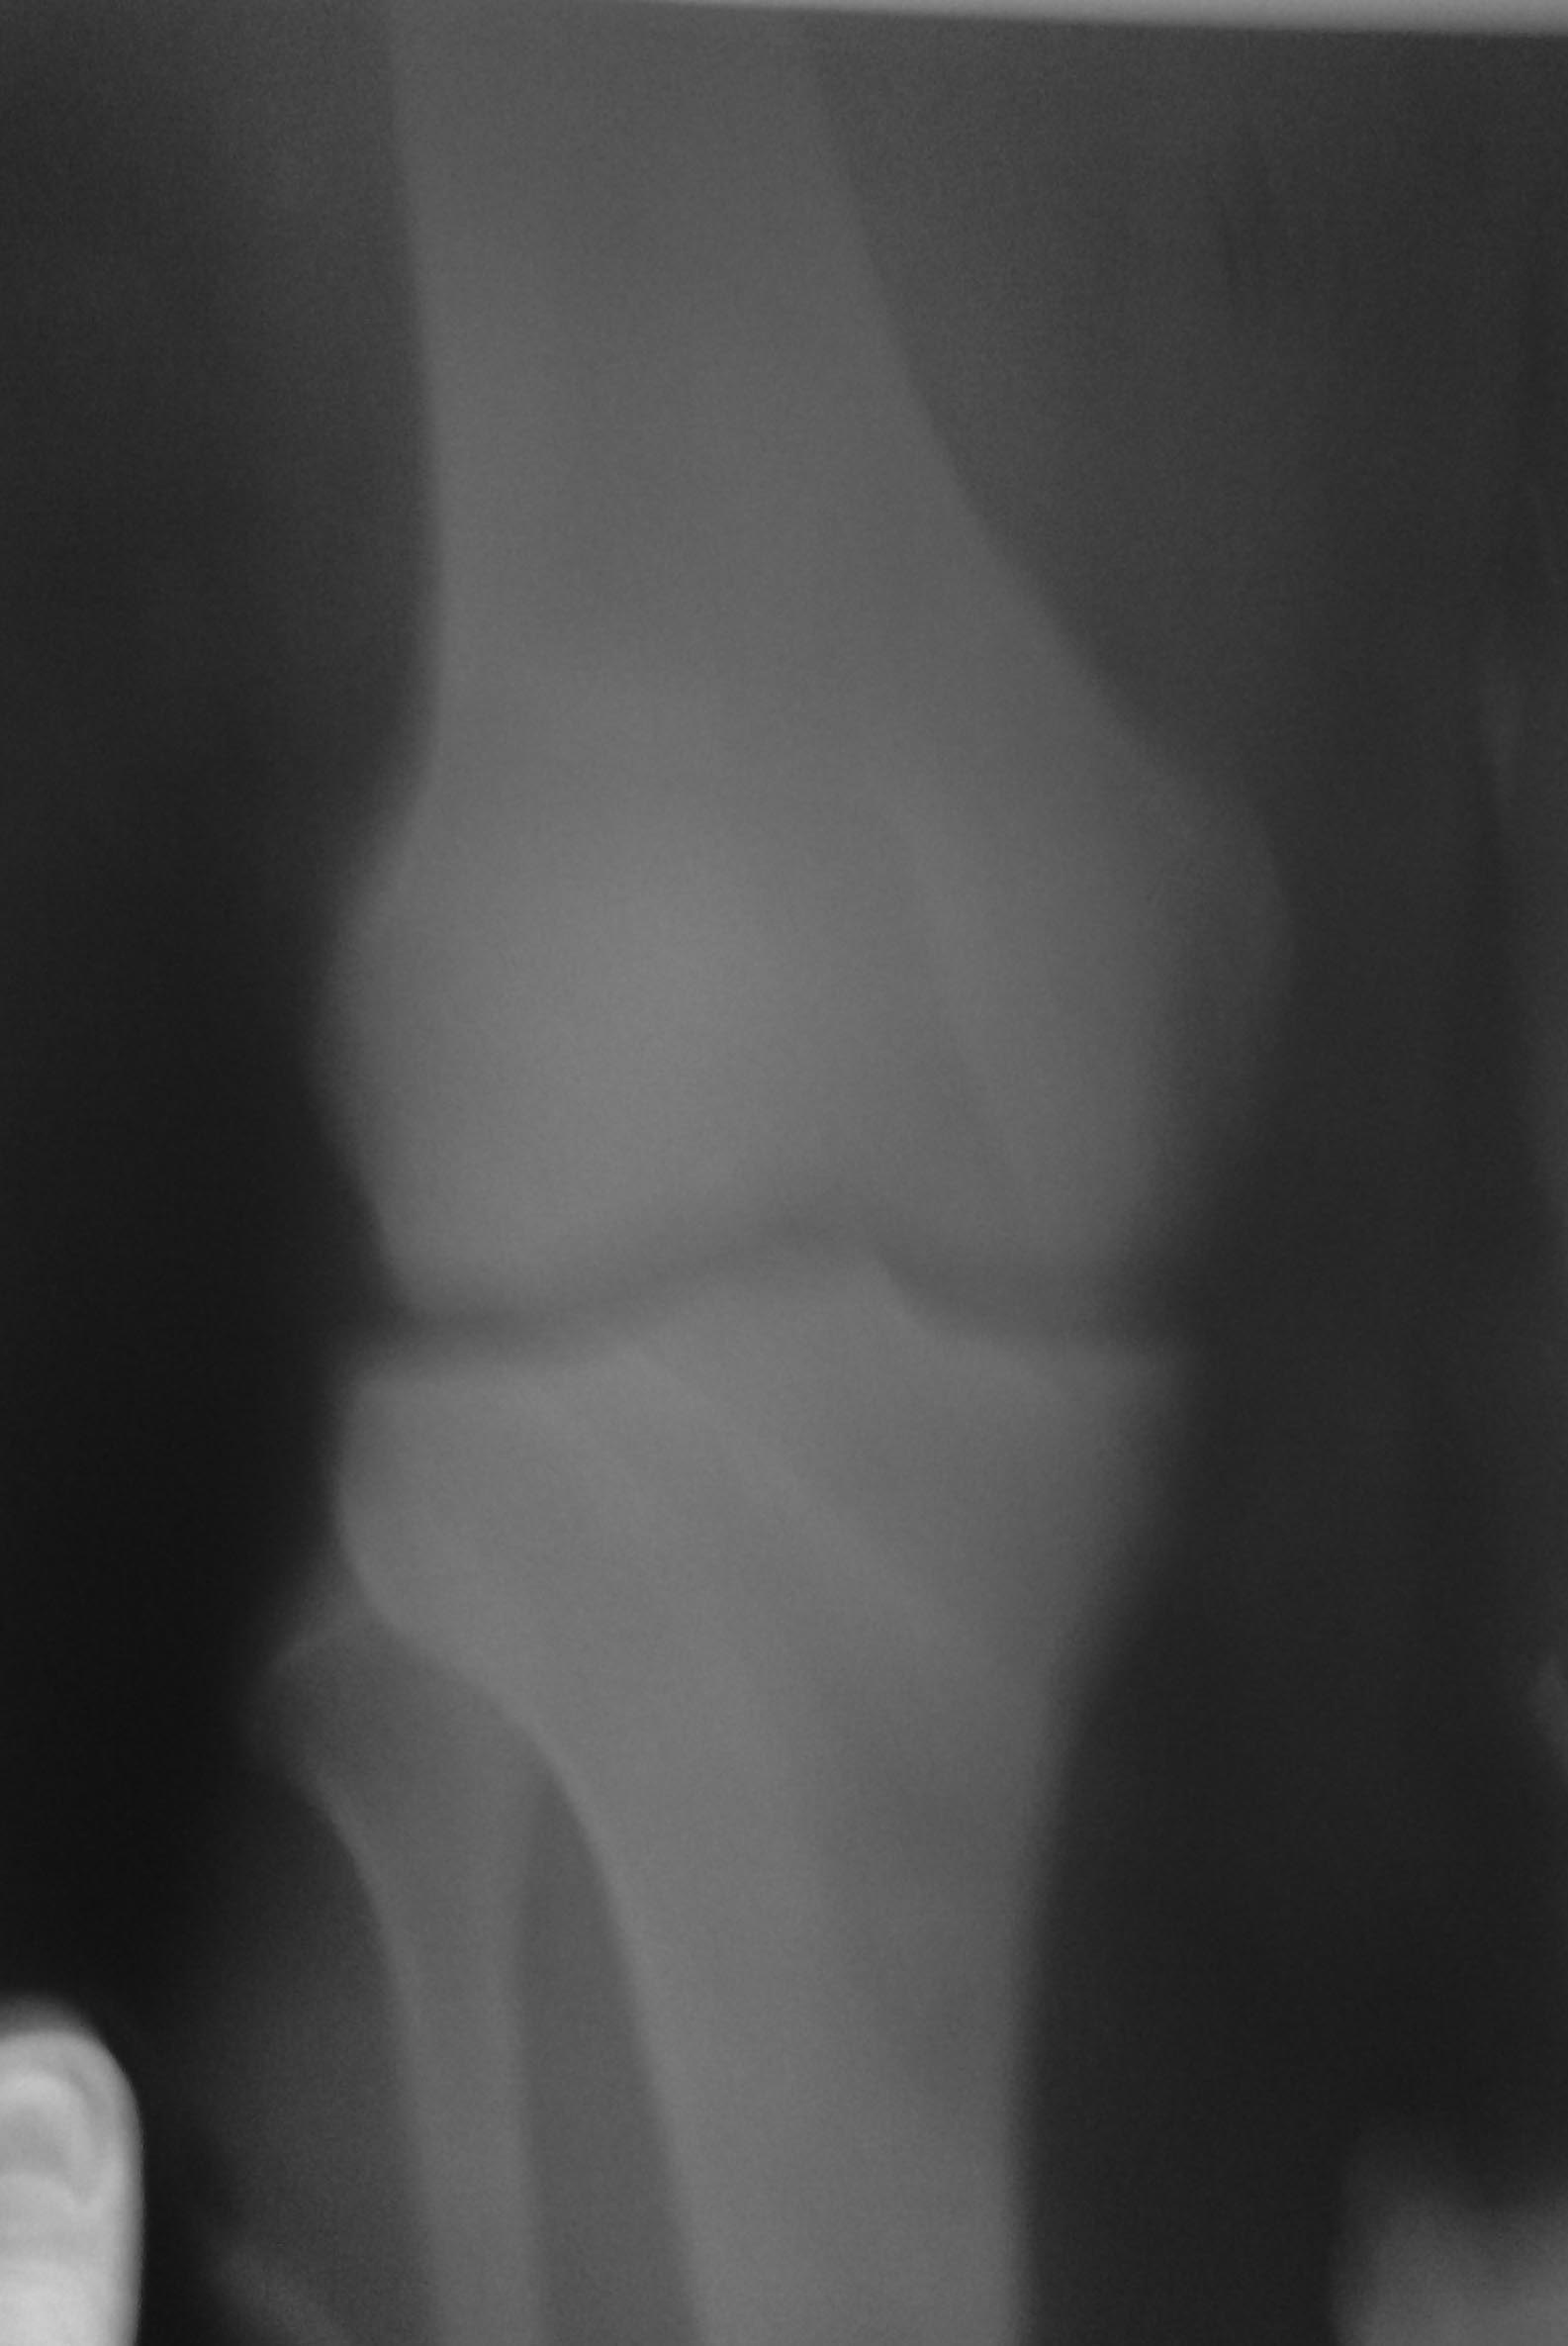

Здравствуйте! Мне 30 лет. Любительски занимаюсь спортом (футбол) с 10 лет. В прошлом году на правой ноге был разрыв ахиллового сухожилия. Спустя год снова начал заниматься футболом, все было нормально, боли в сухожилии не чувствовал. Но во время игры заболело колено. Сказали что артроз. При неловких движениях колена чувствуется боль и нестабильность в суставе. Возможно ли при такой травме продолжать играть? Нужен ли бандаж и не усугубит ли это травму?

По скудному рассказу пациента в три строчки и смазаннной фотографии рентгенограммы определенного суждения о ситуации не составить.

Нужно очно показаться специалисту по спортивной травме, занимающемуся артроскопией коленного сустава. Он колено потестирует, оценит стабильность и другие характеристики, если надо, направит на МРТ. Будет ясна проблема - появятся предложения по ее решению.